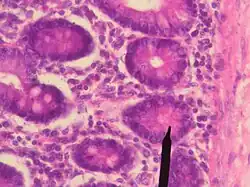

Panethovy buňky jsou exokrinní serózní elementy entodermového původu, které syntetizují proteinopolysacharidové komplexy. Mají jádro při jejich bazální části.[1] Badatelé užívající imunocytochemických metod odkryli, že ve velkých eozinofilních sekrečních granulech těchto buněk, které zabírají většinu cytoplazmy, se nachází lysozym. Panethovy buňky také vylučují defensiny a fosfolipázu A2.[2]

Panethovy buňky se nachází v slizniční membráně tenkého střeva.[1] Jsou umístěny těsně pod střevními kmenovými buňkami v střevních (Lieberkühnových) kryptách.[3] Ojediněle se mohou nacházet v slepém střevě nebo v přívěsku slepého střeva.